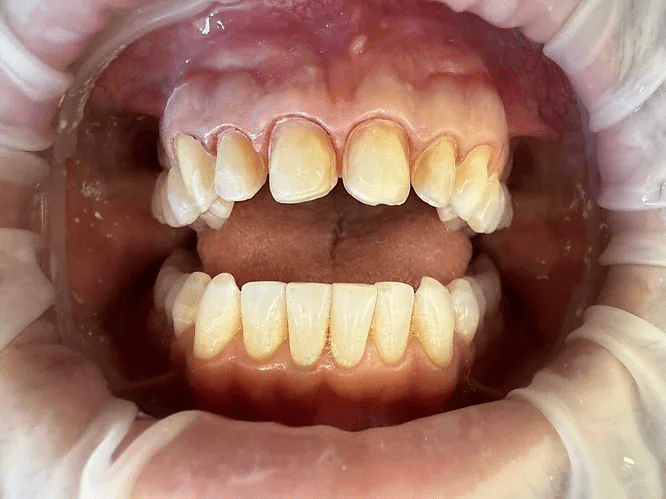

Patients often ask, what do teeth look like behind veneers? The answer can be unsettling. Behind the porcelain shells are teeth that have been shaved down, etched, and permanently altered. They no longer look like natural, full teeth. Instead, they appear reduced and fragile, fully dependent on the veneers covering them.

Contrary to popular belief, porcelain veneers aren’t merely bonded to the front surface of a tooth like a sticker. In reality, the porcelain often wraps under and behind the tooth, altering its structure significantly.

As evident in clinical images, porcelain veneers can cover both the front and back surfaces of the teeth, not just the visible front as commonly advertised.

The degree to which the porcelain extends behind the tooth’s surface varies, but it’s believed to be at least 20%, sometimes more depending on the type of porcelain used.

This wrapping effect can impact speech, chewing function, and create a lingering sense of foreignness in the mouth, especially where the bottom edge of the veneers interacts with the lower teeth.

After veneers are removed, or before the final set is permanently placed for the first time, the underlying teeth are exposed and permanently altered. Because enamel was shaved away during the preparation process, the natural teeth can appear smaller, flatter, or in some cases, sharply reduced.

They are often more sensitive, more vulnerable to damage, and cannot function the same way they did before. The original structure of the tooth is lost, and it cannot grow back.

This is why veneer removal is not a return to your natural smile, but rather an uncovering of a now dependent, altered foundation. This hidden step is rarely shown, which is why before and after photos can be misleading. They do not reveal the permanent cost in between.